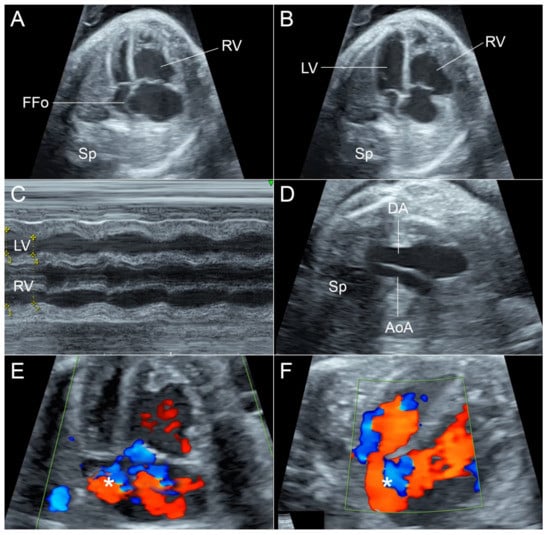

- Reversed flow in aortic arch is commonly seen in hypoplastic left heart or aortic stenosis but in this case the flow crossing the aortic valve shows normal laminar flow.

- Reversed flow in aortic arch is different from that seen in fetal growth restriction (FGR), which usually shows increased afterload (abnormal umbilical blood flow).